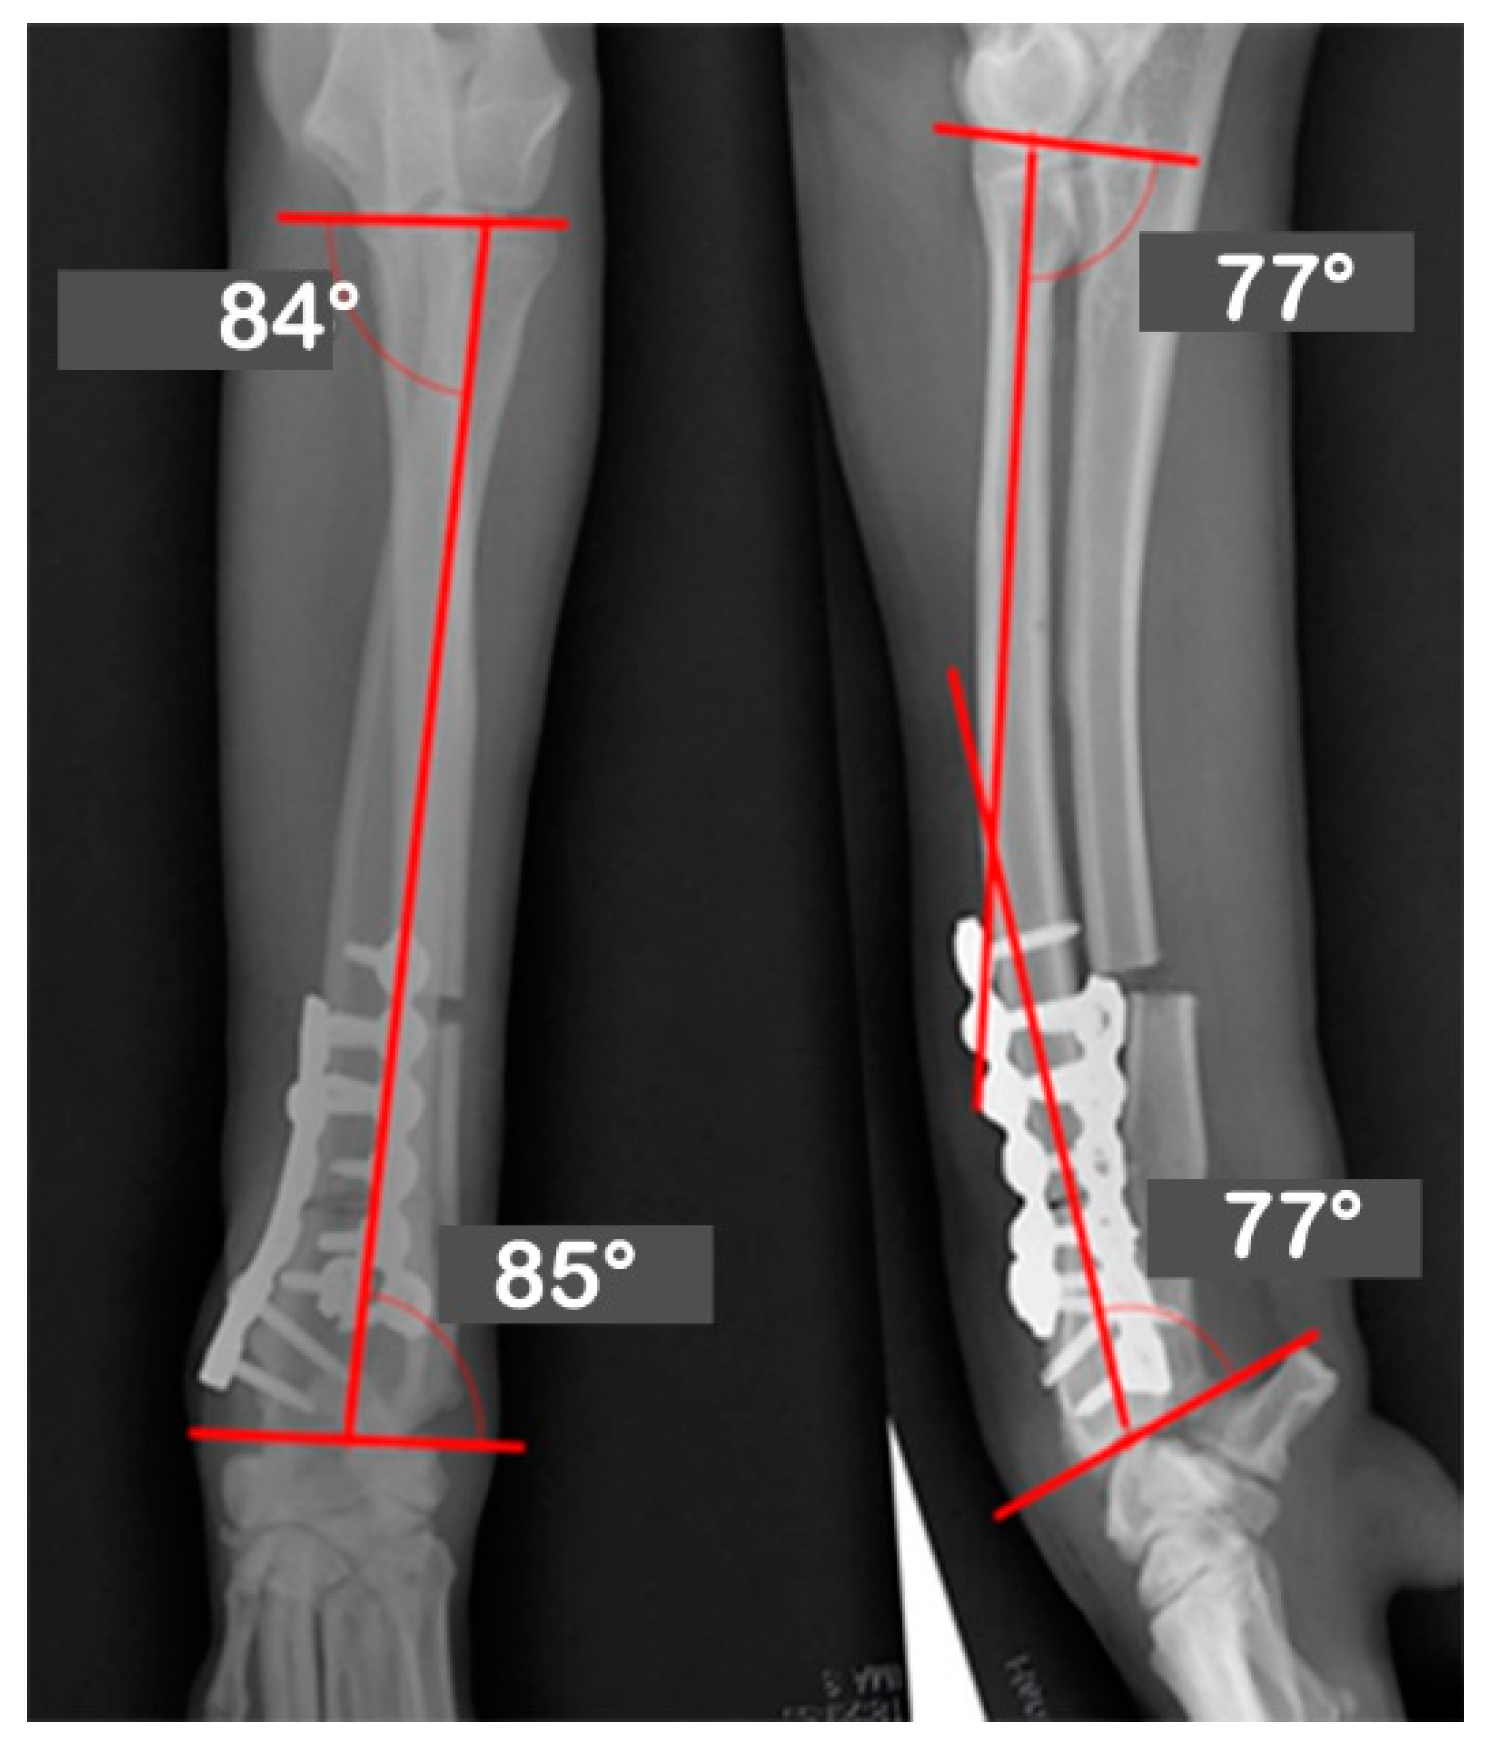

| JOA | Pre-OP | Post-OP | Target | Mean | Reference |

|---|---|---|---|---|---|

| Values | Values | ||||

| aLDRA | 57 | 85 | 85 | 86 | 85~87 |

| aCdPRA | 92 | 87 | 87 | 85 | 84~86 |

| aMPRA | 75 | 84 | 84 | 83 | 82~83 |

| aCdDRA | 62 | 77 | 77 | 77 | 76~78 |

| θ | 38 | 21 | 21 | 27 | 21~32 |